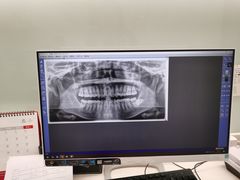

• 厦门医学院附属口腔医院(蔡塘院区)

• -厦门医学院附属口腔医院(蔡塘院区)

肉肉肉肉球 | 21-03-13